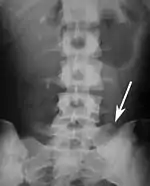

Lumbarization and sacralization

Lumbarization is an anomaly in the spine. It is defined by the nonfusion of the first and second segments of the sacrum. The lumbar spine subsequently appears to have six vertebrae or segments, not five. This sixth lumbar vertebra is known as a transitional vertebra. Conversely the sacrum appears to have only four segments instead of its designated five segments. Lumbosacral transitional vertebrae consist of the process of the last lumbar vertebra fusing with the first sacral segment. [1] While only around 10 percent of adults have a spinal abnormality due to genetics, a sixth lumbar vertebra is one of the more common abnormalities. [2]

Sacralization of the fifth lumbar vertebra (or sacralization) is a congenital anomaly, in which the transverse process of the last lumbar vertebra (L5) fuses to the sacrum on one side or both, or to ilium, or both. These anomalies are observed at about 3.5 percent of people, and it is usually bilateral but can be unilateral or incomplete (ipsilateral or contralateral rudimentary facets) as well. Although sacralization may be a cause of low back pain, it is asymptomatic in many cases (especially bilateral type). Low back pain in these cases most likely occurs due to biomechanics. In sacralization, the L5-S1 intervertebral disc may be thin and narrow. This abnormality is found by X-ray.